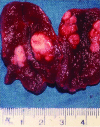

Pediatric endocrine tumors are rare but have fairly characteristic presentations. We describe an approach to diagnosis and management of five of the most common presentations including gonadoblastoma, paraganglioma, medullary thyroid cancer, adrenal cancer, and pituitary adenoma. Genetic testing can aid in the early detection and prevention and management of tumors in patients and in other family members.